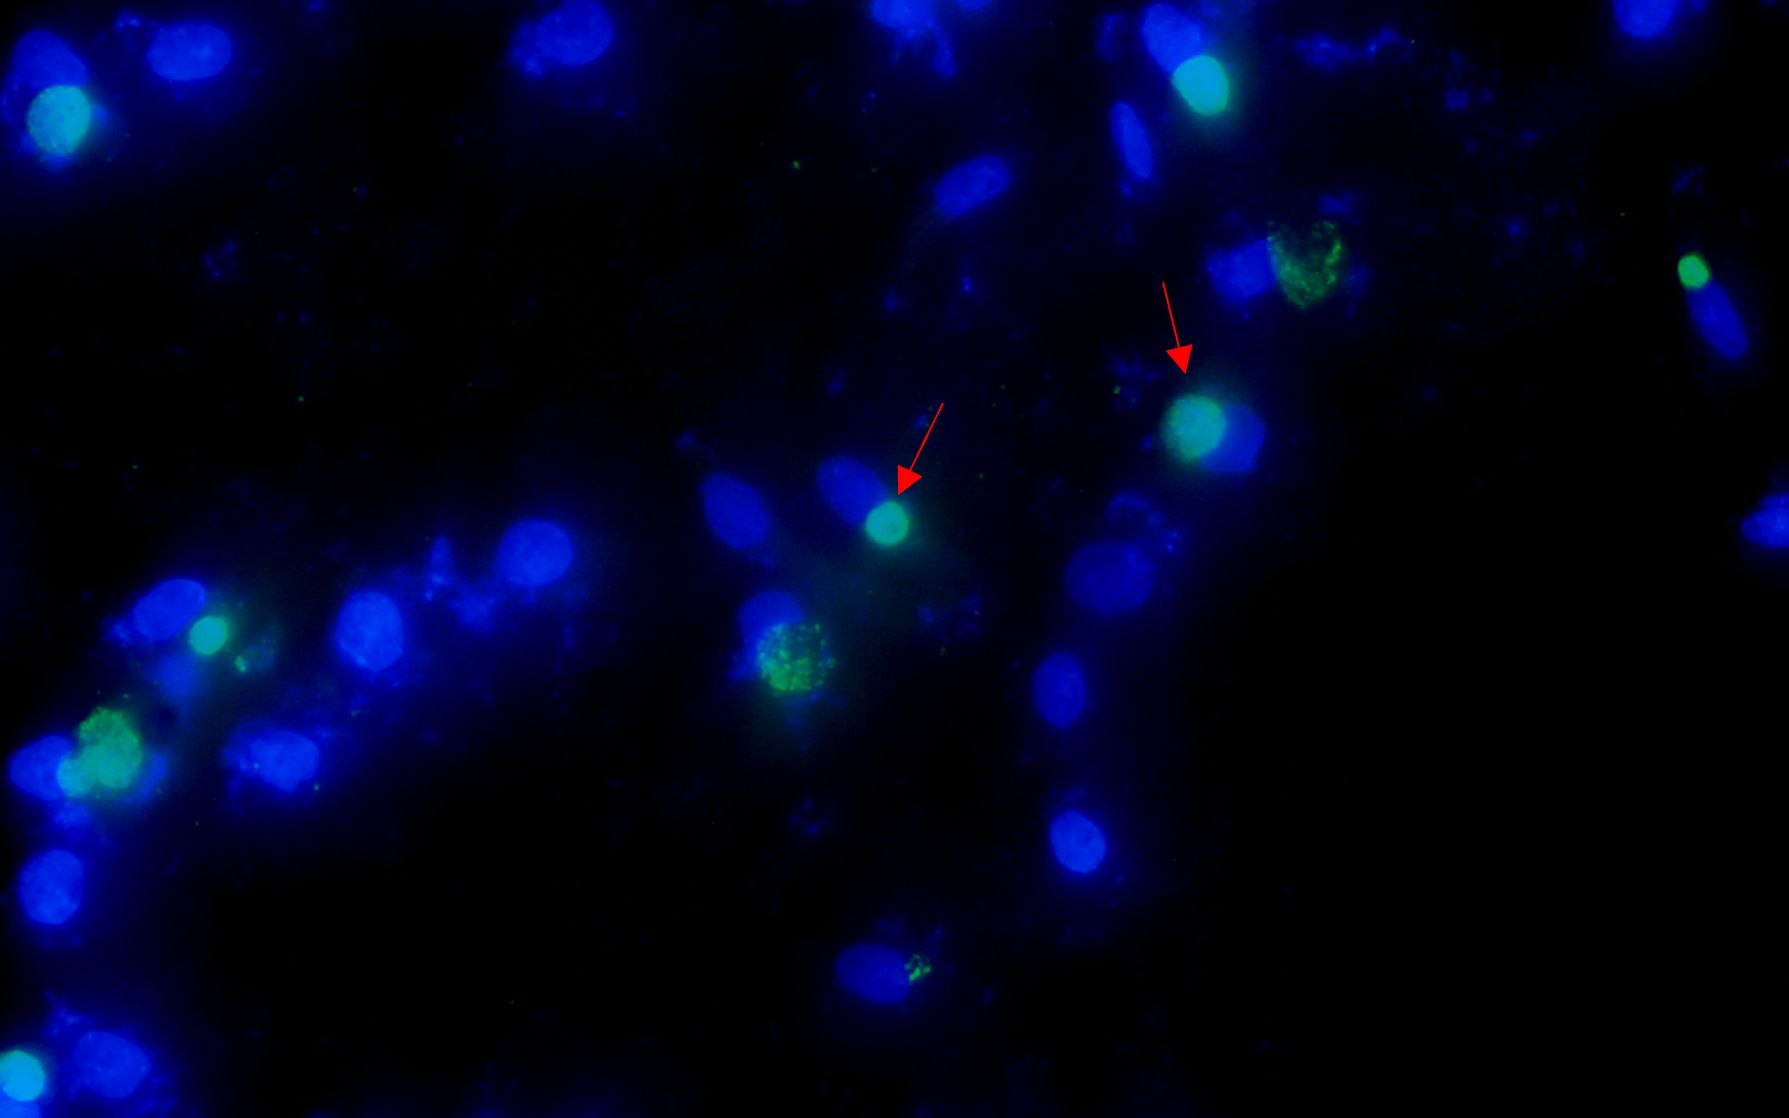

After the patient’s hospital admission, his chest X-ray revealed bilateral pneumonia and ground-glass opacity, and he was prescribed oxygen therapy and doxycycline. Afterward, lesions with ground-glass opacity were reduced, but pulmonary consolidation was still observed in the lungs (Supplementary Figure S2). Based on 23S rDNA amplification, a positive 172-bp band of C. psittaci was detected in the patient’s alveolar wash, while his tracheal mucosa and throat swabs were negative (Figure 1A). Other family members, the nurses, the attending physician, and the house chickens were negative for C. psittaci (Figure 1B). Afterward, qPCR results showed that the patient’s alveolar wash was positive for C. psittaci. Subsequently, positive C. psittaci was identified in the patient’s alveolar wash and throat swab, and his sons’ throat swab. However, a negative reaction was found in his tracheal mucosa and other close contacts’ samples (Figure 2). The ompA gene sequence of the C. psittaci strain was determined and submitted to GenBank (accession number: OR616243). After inoculation into SPF embryonated eggs, typical intracellular inclusions were observed using immunofluorescence staining (Figure 3).

Figure 3. Positive Chlamydia psittaci strain was isolated from patient’s throat swab samples using immunofluorescence staining. Blue, 4',6-diamidino-2-phenylindole (DAPI)-stained host cells. Green, fluorescein isothiocyanate (FITC)-labeled lipopolysaccharide (LPS) antibody against Chlamydia.